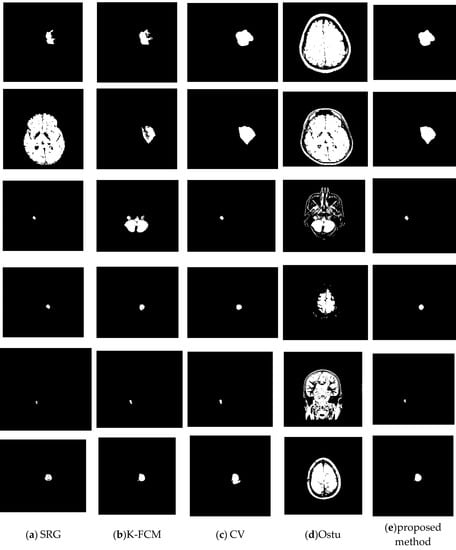

To verify the effectiveness of the proposed method, we randomly selected some images to test. For each brain tumor cross-sectional image, we compared the results of each algorithm with the results of manual segmentation. Figure 8 is the original image. Figure 9 shows the visualization results obtained by the proposed algorithm, CV, K-FCM [], Ostu [] and region growing algorithm [] for brain tumor segmentation. The experimental results of the threshold algorithm were obtained by manually adjusting the threshold parameters several times. Except for the algorithm in this paper, the other methods could not fully achieve automated detection and segmentation. From Table 2, we can observe the quantitative results of the four detection algorithms for brain tumor. When Accuracy, JSC and DSC were higher, it indicated that the prediction accuracy of the target was higher. The proposed method outperformed other algorithms on Accuracy, JSC, and DSC. Therefore, from the comprehensive analysis in Figure 9 and Table 2, it can be seen that the algorithm in this study had high accuracy in detecting and segmenting brain tumors. The proposed method has certain competitiveness compared with other classical algorithms, and is expected to provide a reliable reference for clinical decision-making. In addition, as is shown in Table 3, there are significant differences between the proposed model and other models.

Figure 9.

Comparison of the proposed method with others. (a) SRG. (b) K-FCF. (c) CV. (d) Ostu. (e) The proposed method.